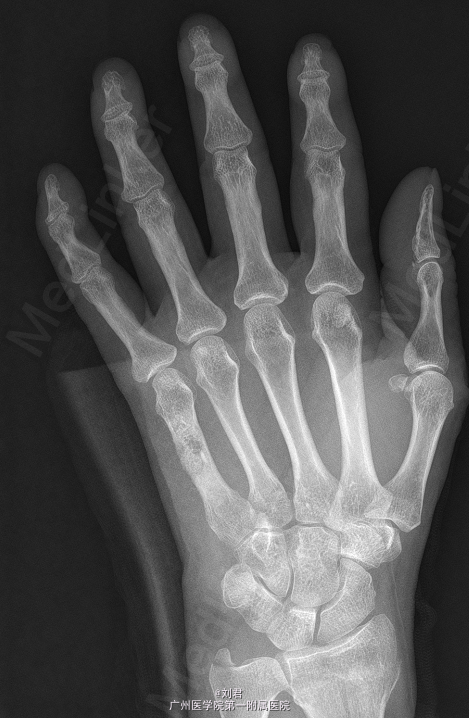

患者,女,51岁,因“摔伤致左腕肿痛伴活动障碍7天”入院。 患者7天前摔伤,左掌着地,致昨晚疼痛,疼痛为持续性,较剧,能忍,伴左腕活动障碍.

左腕石膏托固定,左腕肿胀,无明显畸形,压痛明显,左腕活动障碍,左手各指血运好,感觉正常,活动可。

初步诊断:1、 左桡骨远端骨折,2、左手第5掌骨软骨类肿瘤。在臂丛复合静脉麻醉下行“左掌骨内生软骨瘤切除术”,手术过程顺利,术后予以对症治疗。